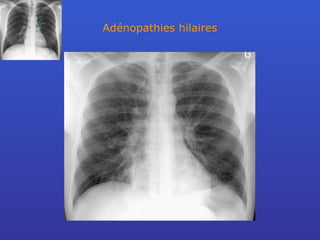

Adénopathies hilaires